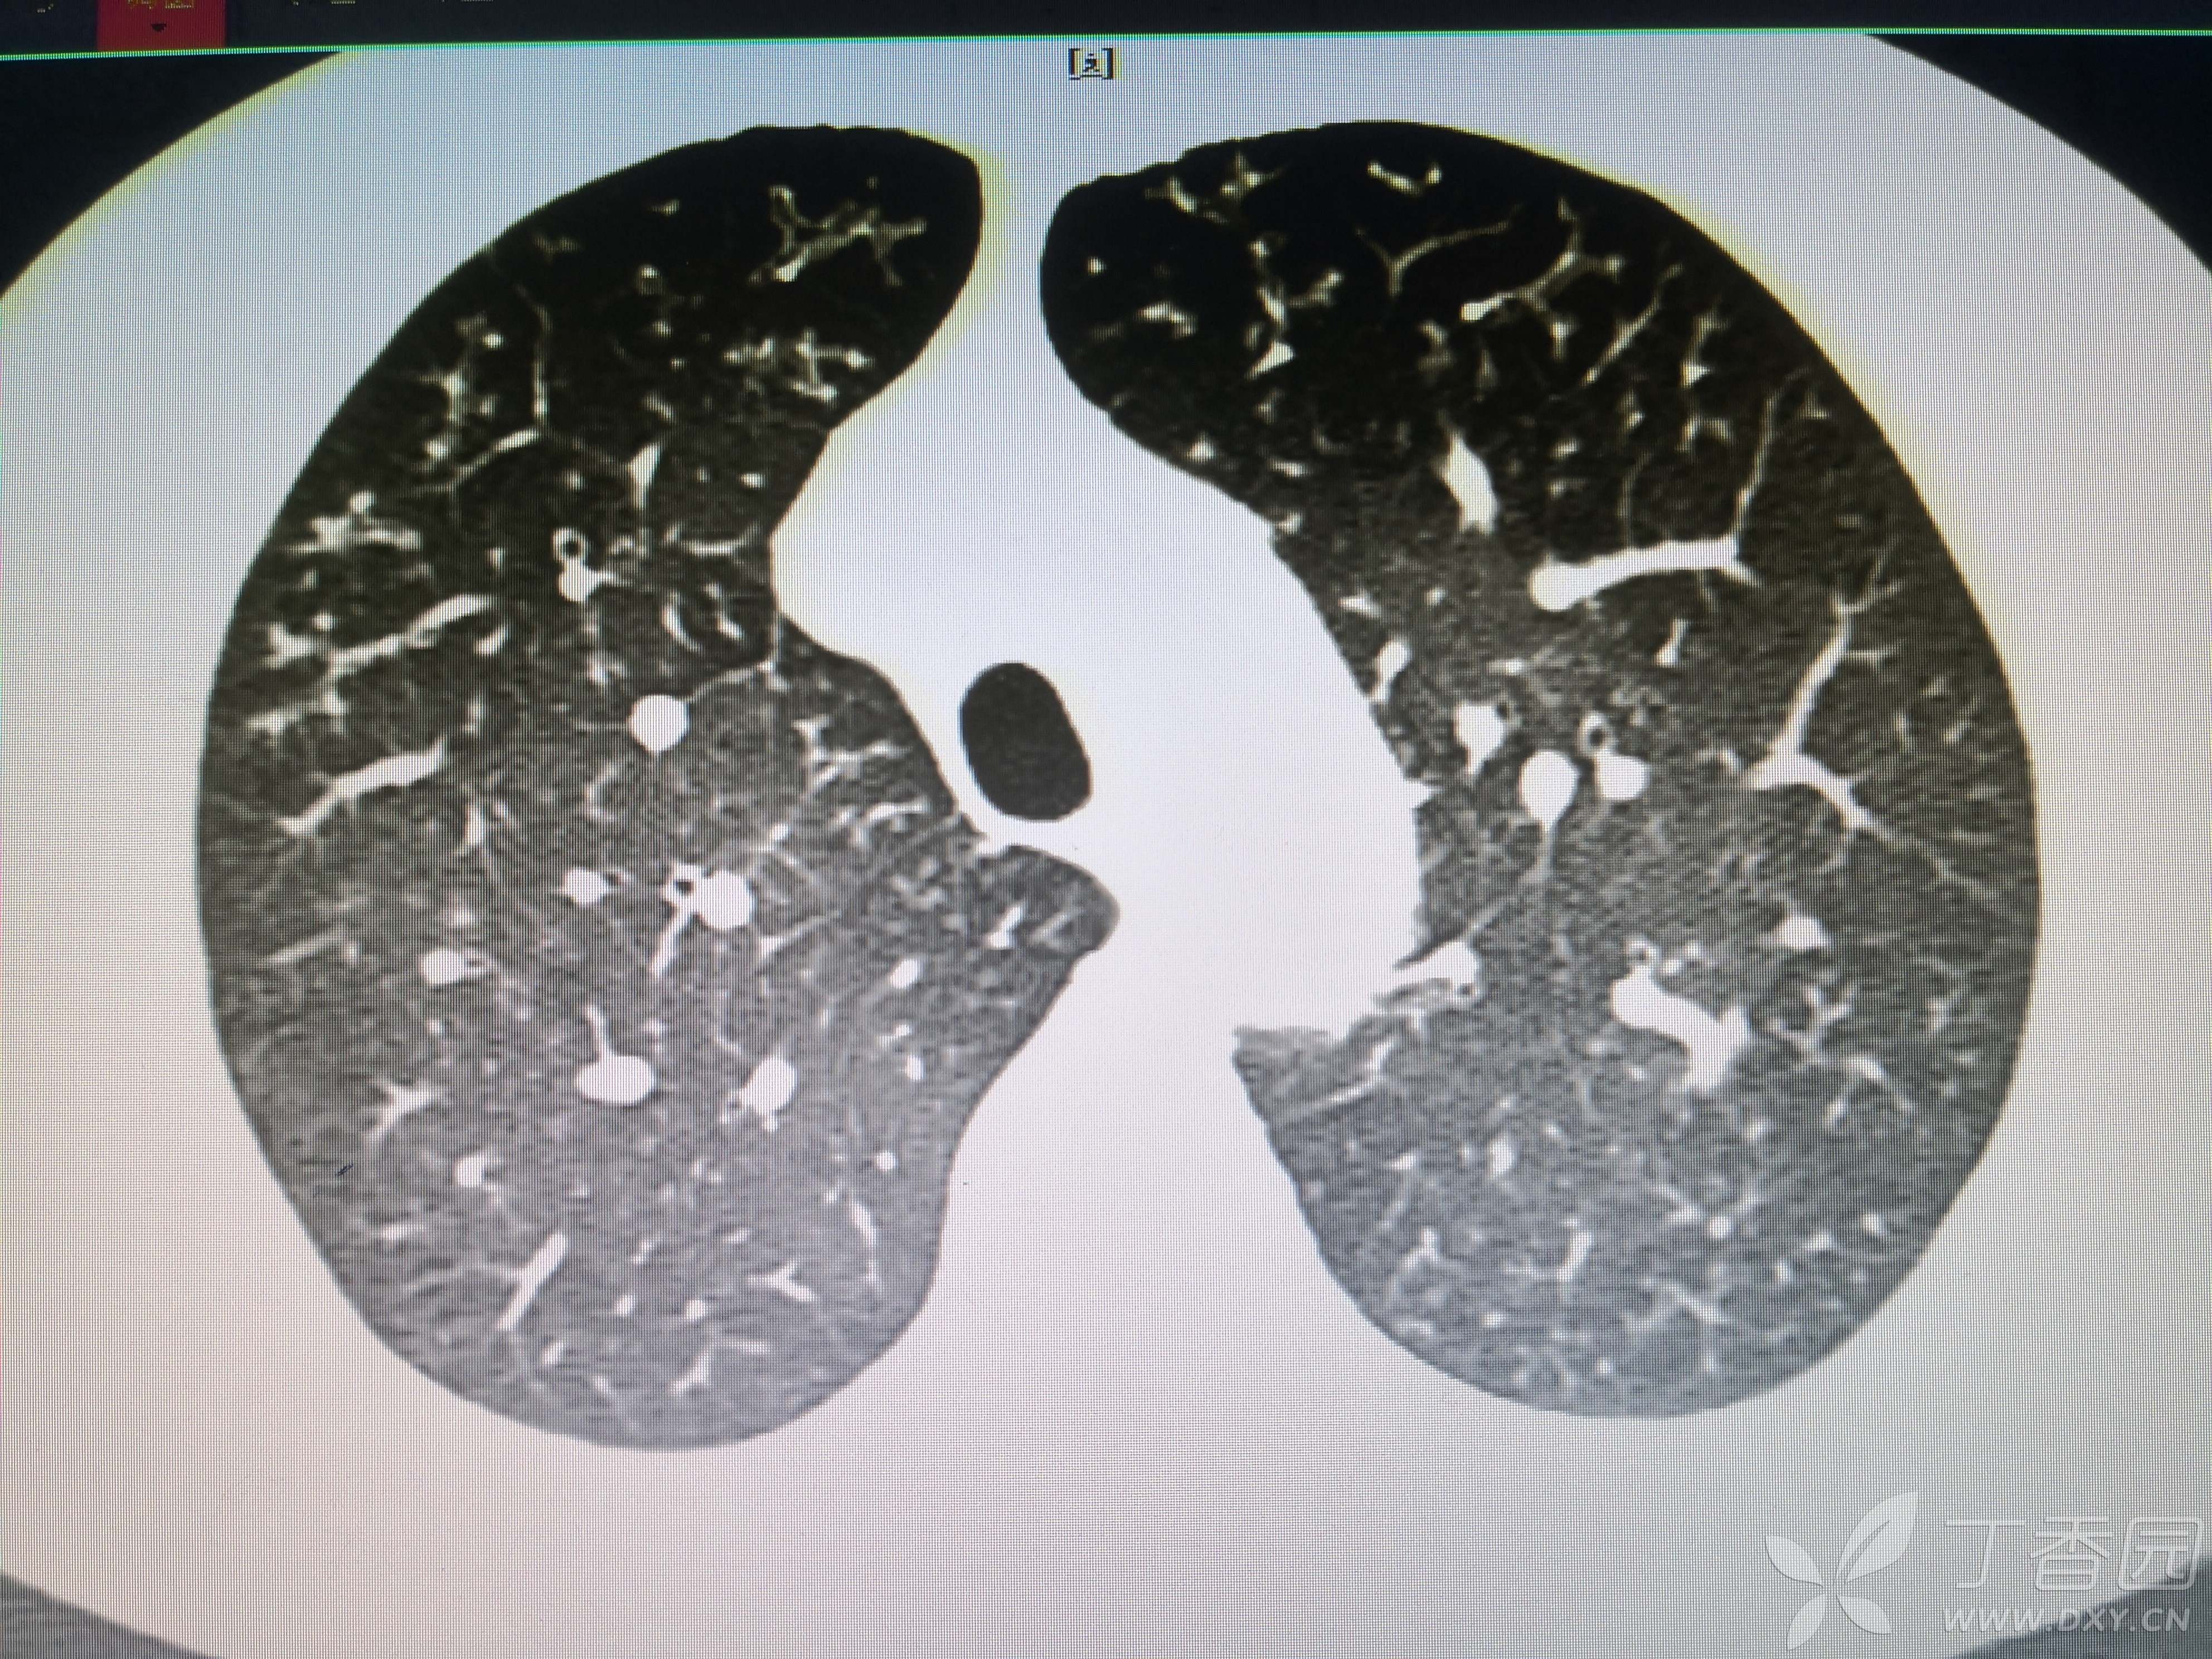

患者性别:女

患者年龄:54岁

简要病史:反复咳嗽、咳脓痰40余年,气喘10年,加剧2周。

体格检查:SpO2:72%,双中下肺闻及中小湿啰音。

辅助检查:见图

临床诊断:支气管扩张并感染

治疗经过:哌拉西林他坐巴坦联合左氧氟沙星抗感染